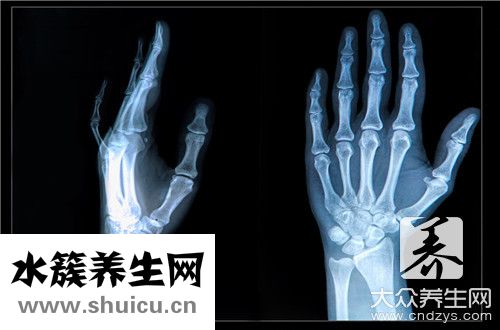

(0)那是身體手腕周邊的骨頭,是敏感的骨頭,在大家的生活中很容易發生0 )骨折這種狀況。 如果發生左手舟骨骨折這樣的情況,對身體的影響非常大,另外左手舟骨骨折的治療也不方便,所以需要特別重視,下面我們來詳細調查一下左手舟骨骨折怎么樣治療。

1,手舟骨骨折很容易壞死,這個是手舟骨骨折最不便的地區!務必管形石膏固定最少8個周乃至更久!2,手舟骨骨折斷端一般 無挪動,可是血液循環系統十分受到限制,因此 隨時隨地觀查是不是壞死,一但壞死馬上手術治療切除!3,石膏固定期內,堅持不懈康復訓練!管形熟石膏由于是密閉式的,里邊免不了瘙癢,請別用東西塞進去抓,防止抓爛感染,用乙醇侵潤就可以了!

有關手舟骨折的醫治標準 :1)異常手舟骨骨折而X線片末見骨折線者,先要按骨折開展固定不動,2星期過后線片復診,如果沒有骨折,已不固定不動,若有骨折,則應再次連續固定不動,直到骨折愈合;(2)無挪動骨折者,能用無墊片短臂管形石膏固定上臂旋前,腕背伸30°橈偏,及大拇指對掌位6~8周或更長期;

(3)有挪動骨折或陳舊性骨折行得通橈骨莖突摘除,內固定不動或植骨術術,石膏固定至痊愈;(4)骨折不愈合或腦缺血壞死,行得通血管種植,或手舟骨摘除,或行肘關節結合